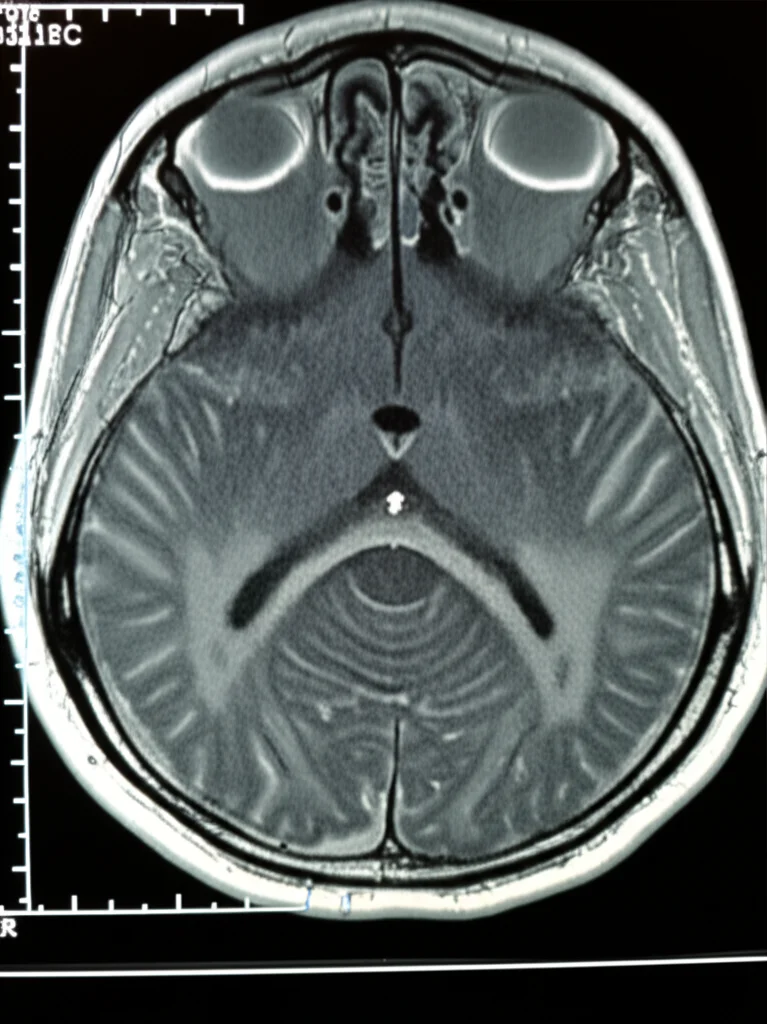

A questo punto, con i risultati ricorrenti e una persistente moderata instabilità dell’andatura, si decide per una risonanza magnetica cerebrale. E qui, la scoperta che nessuno si aspettava: metastasi cerebrali cistiche disseminate, sia a livello infratentoriale che sopratentoriale. La massa più grande comprimeva le strutture mediane del cervelletto e il quarto ventricolo. Un intervento chirurgico d’urgenza per la resezione della massa cerebellare sinistra rivela la natura di queste metastasi: un adenocarcinoma polmonare, fino a quel momento sconosciuto, positivo al fattore di trascrizione tiroideo 1 (TTF1). Una diagnosi terribile, che getta una luce completamente diversa su quei sintomi iniziali.